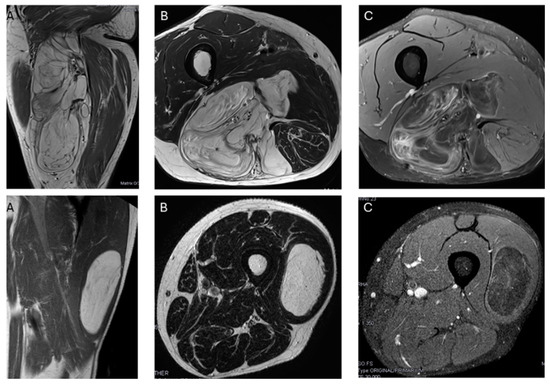

There was typically more than one non-fat nodule in ALT, while lipomas usually had only one (Figure 6). Unlike other studies, which suggested that non-fat nodules larger than 1 cm in diameter are an important discriminator favoring ALT over lipoma [17], our findings did not support this distinction.

Figure 6.

Nodules. Sagittal T1W images show a deep lipomatous mass in the popliteal fossa, measuring 27 cm along its long axis and with two non-fat nodules (arrows) Diagnosis: ALT (MDM2 positive). Axial T2W images present a lipomatous tumor in quadriceps, with two non-fat nodules (asterisks) Diagnosis: ALT (MDM2 positive).

We do not know the exact explanation for these results, but ALTs are generally larger than lipomas, which may explain why they tend to have more than one non-fat nodule, although these nodules are not significantly larger in ALTs than in lipomas.